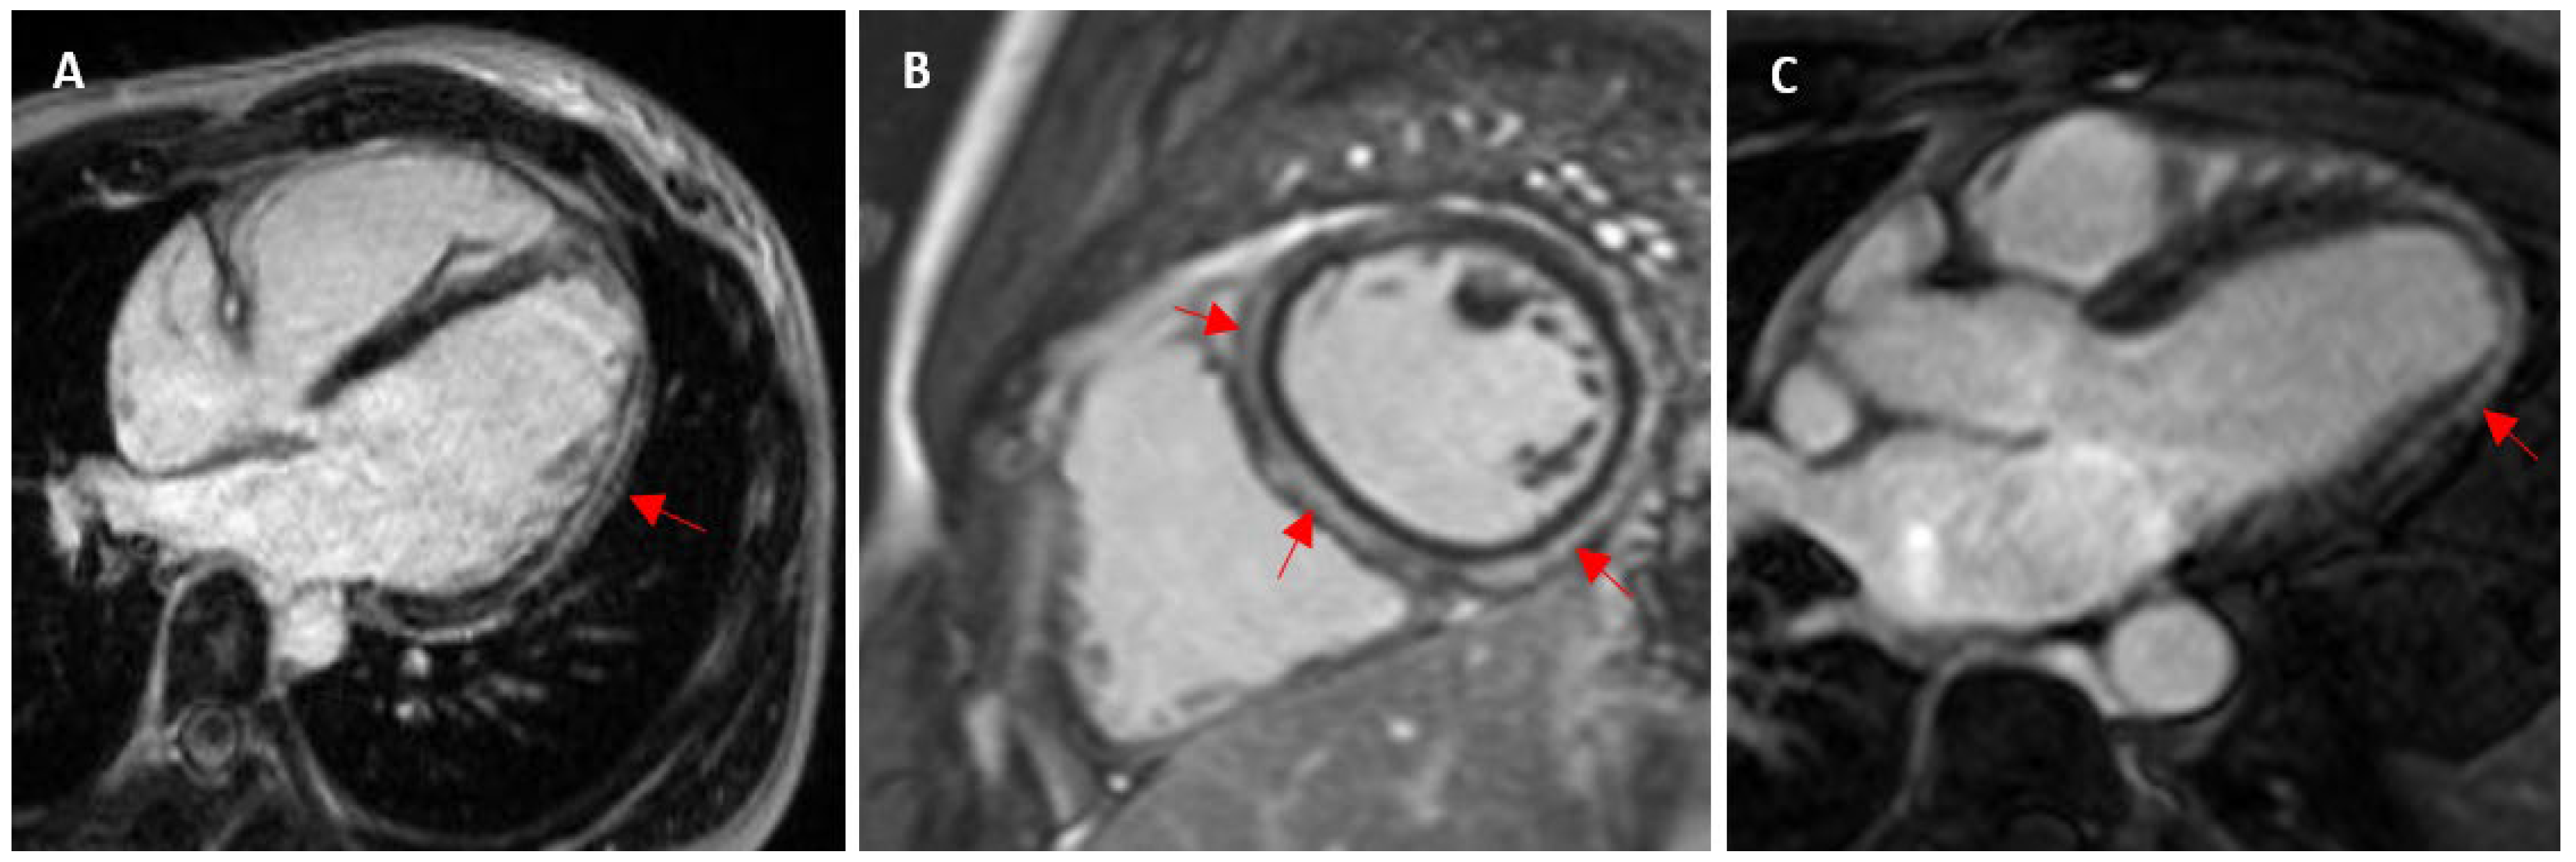

- Cummings, K.W.; Bhalla, S.; Javidan-Nejad, C.; Bierhals, A.J.; Gutierrez, F.R.; Woodard, P.K. A pattern-based approach to assessment of delayed enhancement in nonischemic cardiomyopathy at MR imaging. Radiographics 2009, 29, 89–103. [Google Scholar] [CrossRef] [PubMed]

- Wilson, M.; O’Hanlon, R.; Prasad, S.; Deighan, A.; MacMillan, P.; Oxborough, D.; Godfrey, R.; Smith, G.; Maceira, A.; Sharma, S.; et al. Diverse patterns of myocardial fibrosis in lifelong, veteran endurance athletes. J. Appl. Physiol. 2011, 110, 1622–1626. [Google Scholar] [CrossRef]

- Breuckmann, F.; Möhlenkamp, S.; Nassenstein, K.; Lehmann, N.; Ladd, S.; Schmermund, A.; Sievers, B.; Schlosser, T.; Jöckel, K.-H.; Heusch, G.; et al. Myocardial late gadolinium enhancement: Prevalence, pattern, and prognostic relevance in marathon runners. Radiology 2009, 251, 50–57. [Google Scholar] [CrossRef]

| Wilson et al. (2011) [20] 1.5 T | 29 12 lifelong veteran endurance and 17 young endurance: marathon, ultramarathon, ironman, triathlon | Veteran: 43 ± 6 y of competitive training Young: 18 ± 7 y of competitive training | 57 ± 6 31 ± 5 | M: 100 1.96 ± 0.14 2 ± 0.14 | Veteran: 6/12 (50%) Young: 0/17 Total: 6/29 (20.7%) | 1 CAD pattern: subendocardial septal and lateral wall infarction pattern 5 non-CAD pattern: 1 subepicardial lateral wall (myocarditis), 4 junctional: basal and mid insertion point, inferior insertion point and mid/apical, inferior mid/apical insertion point, inferior insertion point | - | - |

| Breuckmann et al. (2009) [24] 1.5 T | 102 Marathon runners | ≥5 marathons in ≤3 y | 57 ± 6 | M: 100 | 12/102 (11.8%) | 5: subendocardial layer typical myocardial infarction (10 LAD, 1 LCA, 3 RCA segments) 7: mid-myocardial patchy nonischaemic pattern (3 LAD, 5 LCA, 9 RCA segments) | - | - |